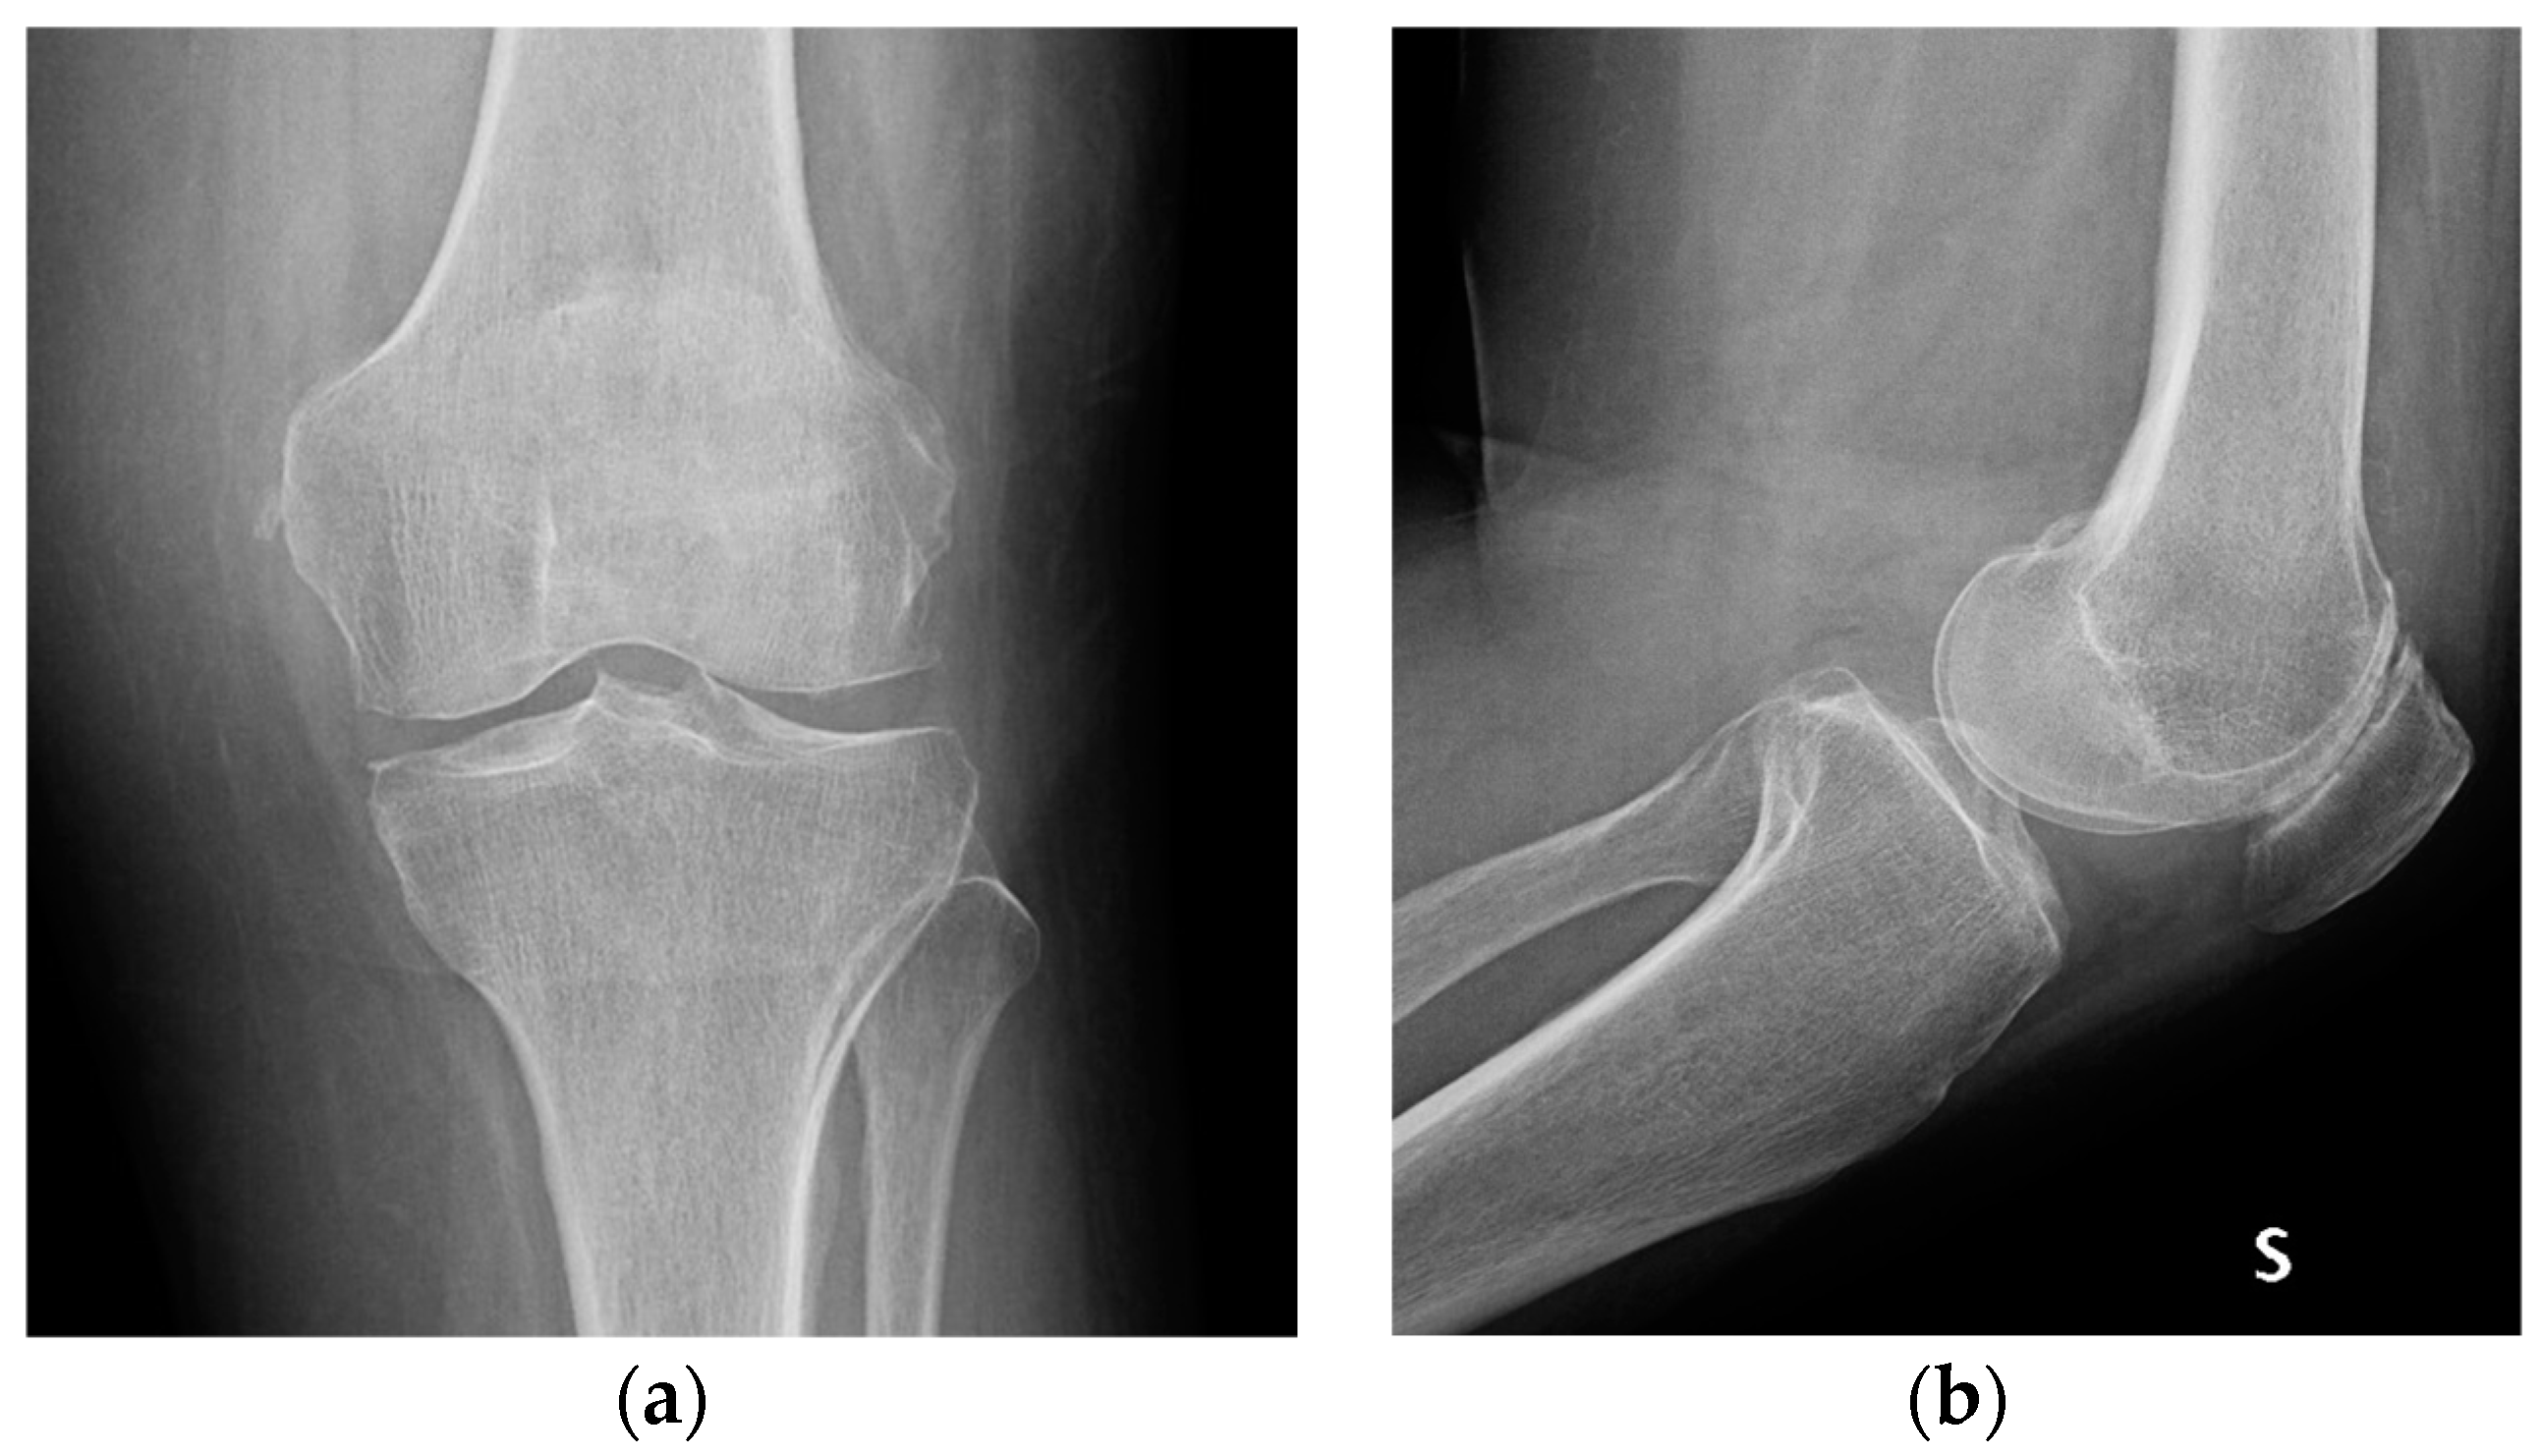

| Stage I | Opacity of fluid, redness of the synovial membrane, possible petechial bleeding, no radiological alterations |

| Stage II | Severe inflammation, fibrinous deposition, pus, no radiological alterations |

| Stage III | Thickening of the synovial membrane, compartment formation (“sponge-like” arthroscopic view, especially in the suprapatellar pouch), no radiological alterations |

| Stage IV | Aggressive pannus with infiltration of the cartilage, possibly undermining the cartilage, radiological signs of subchondral osteolysis, possible osseous erosions and cysts |